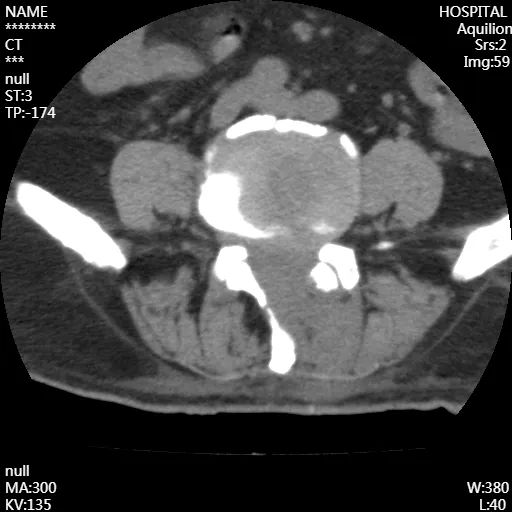

腰椎CT成像

從影像上看出,患者術(shù)后神經(jīng)壓迫情況得到了改善